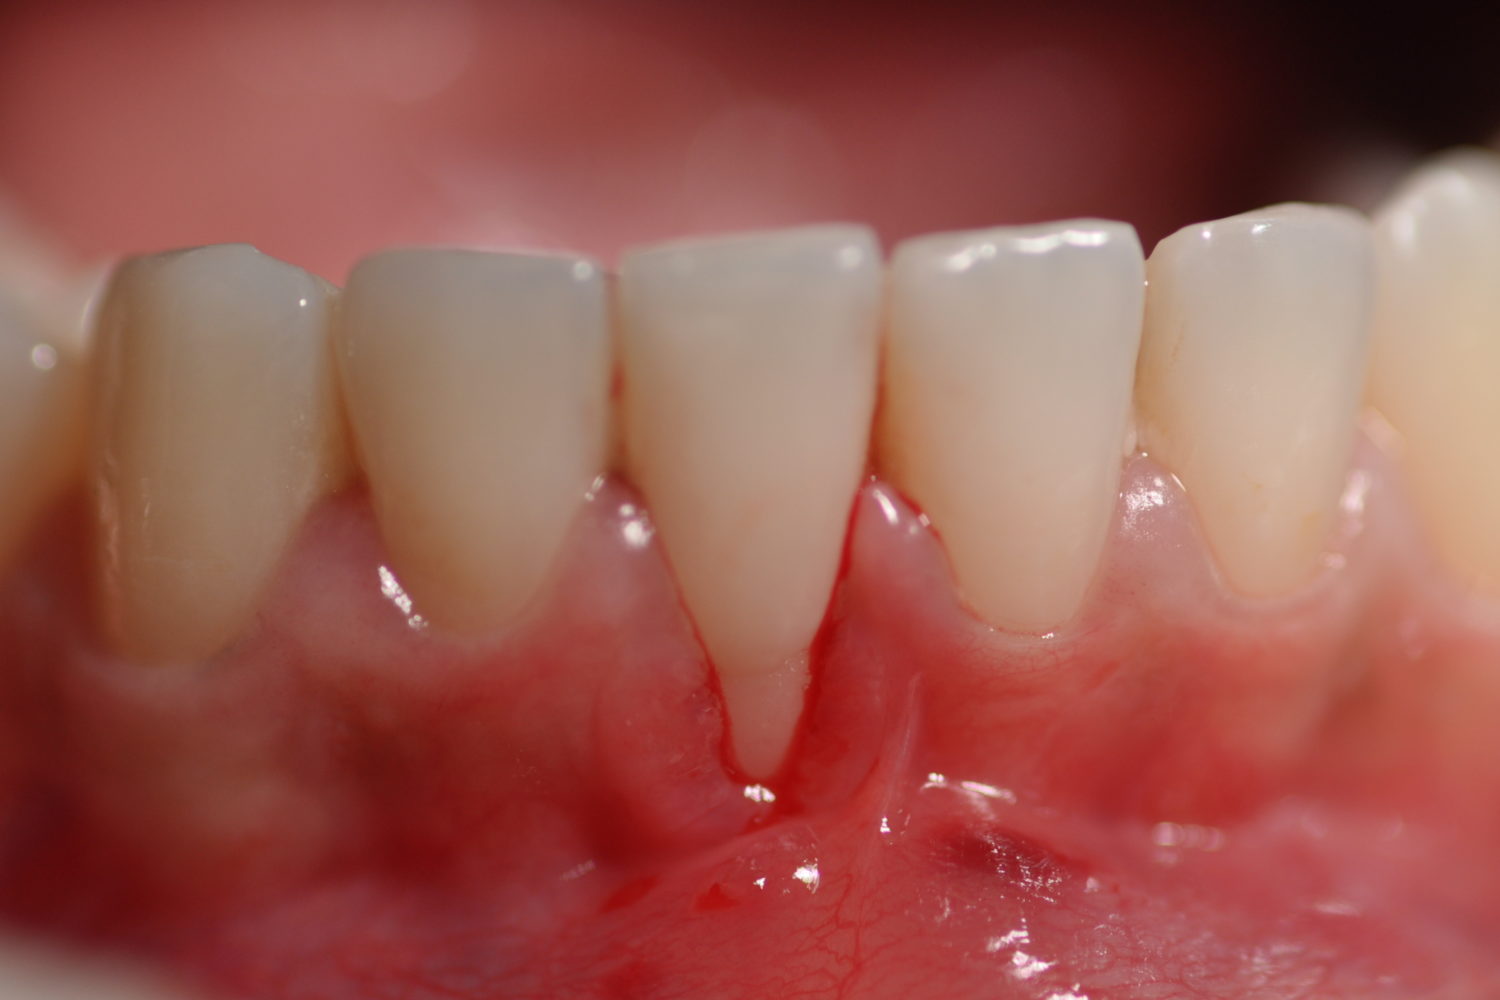

Retração Gengival: A retração gengival ocorre quando a gengiva se retrai e expõe a raiz do dente.

Isso pode ser causado por escovação agressiva, periodontite ou fatores genéticos.

Doenças Periodontais: Doenças como a gengivite e a periodontite podem causar retração gengival e exposição da raiz do dente.

Sinais de Raiz do Dente Exposta:

Os sinais de raiz do dente exposta podem incluir:

- Sensibilidade ao calor, frio e alimentos doces.

- Dor ao mastigar ou ao tocar na região afetada.

- Gengivas sensíveis ou inflamadas.

- Aparência amarelada ou escurecida da raiz exposta.

- Maior risco de cáries na região exposta.